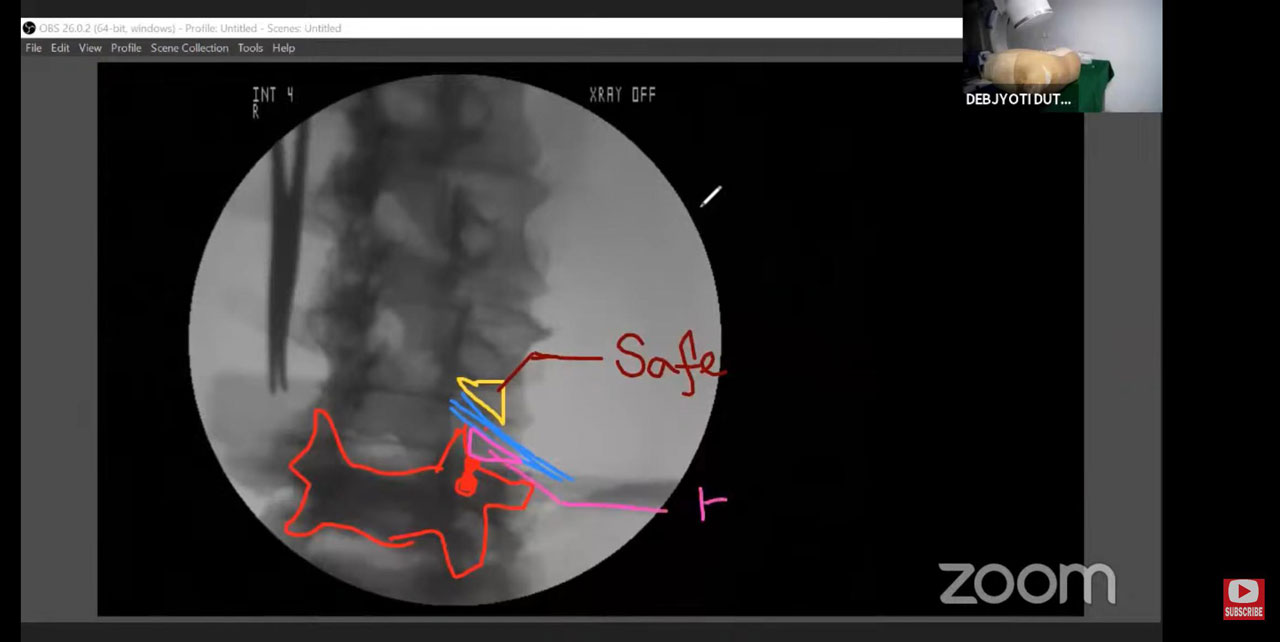

Epidural Injection

Root Block

Radio Frequency Ablation

Joint & Nerve Hydro Dissection